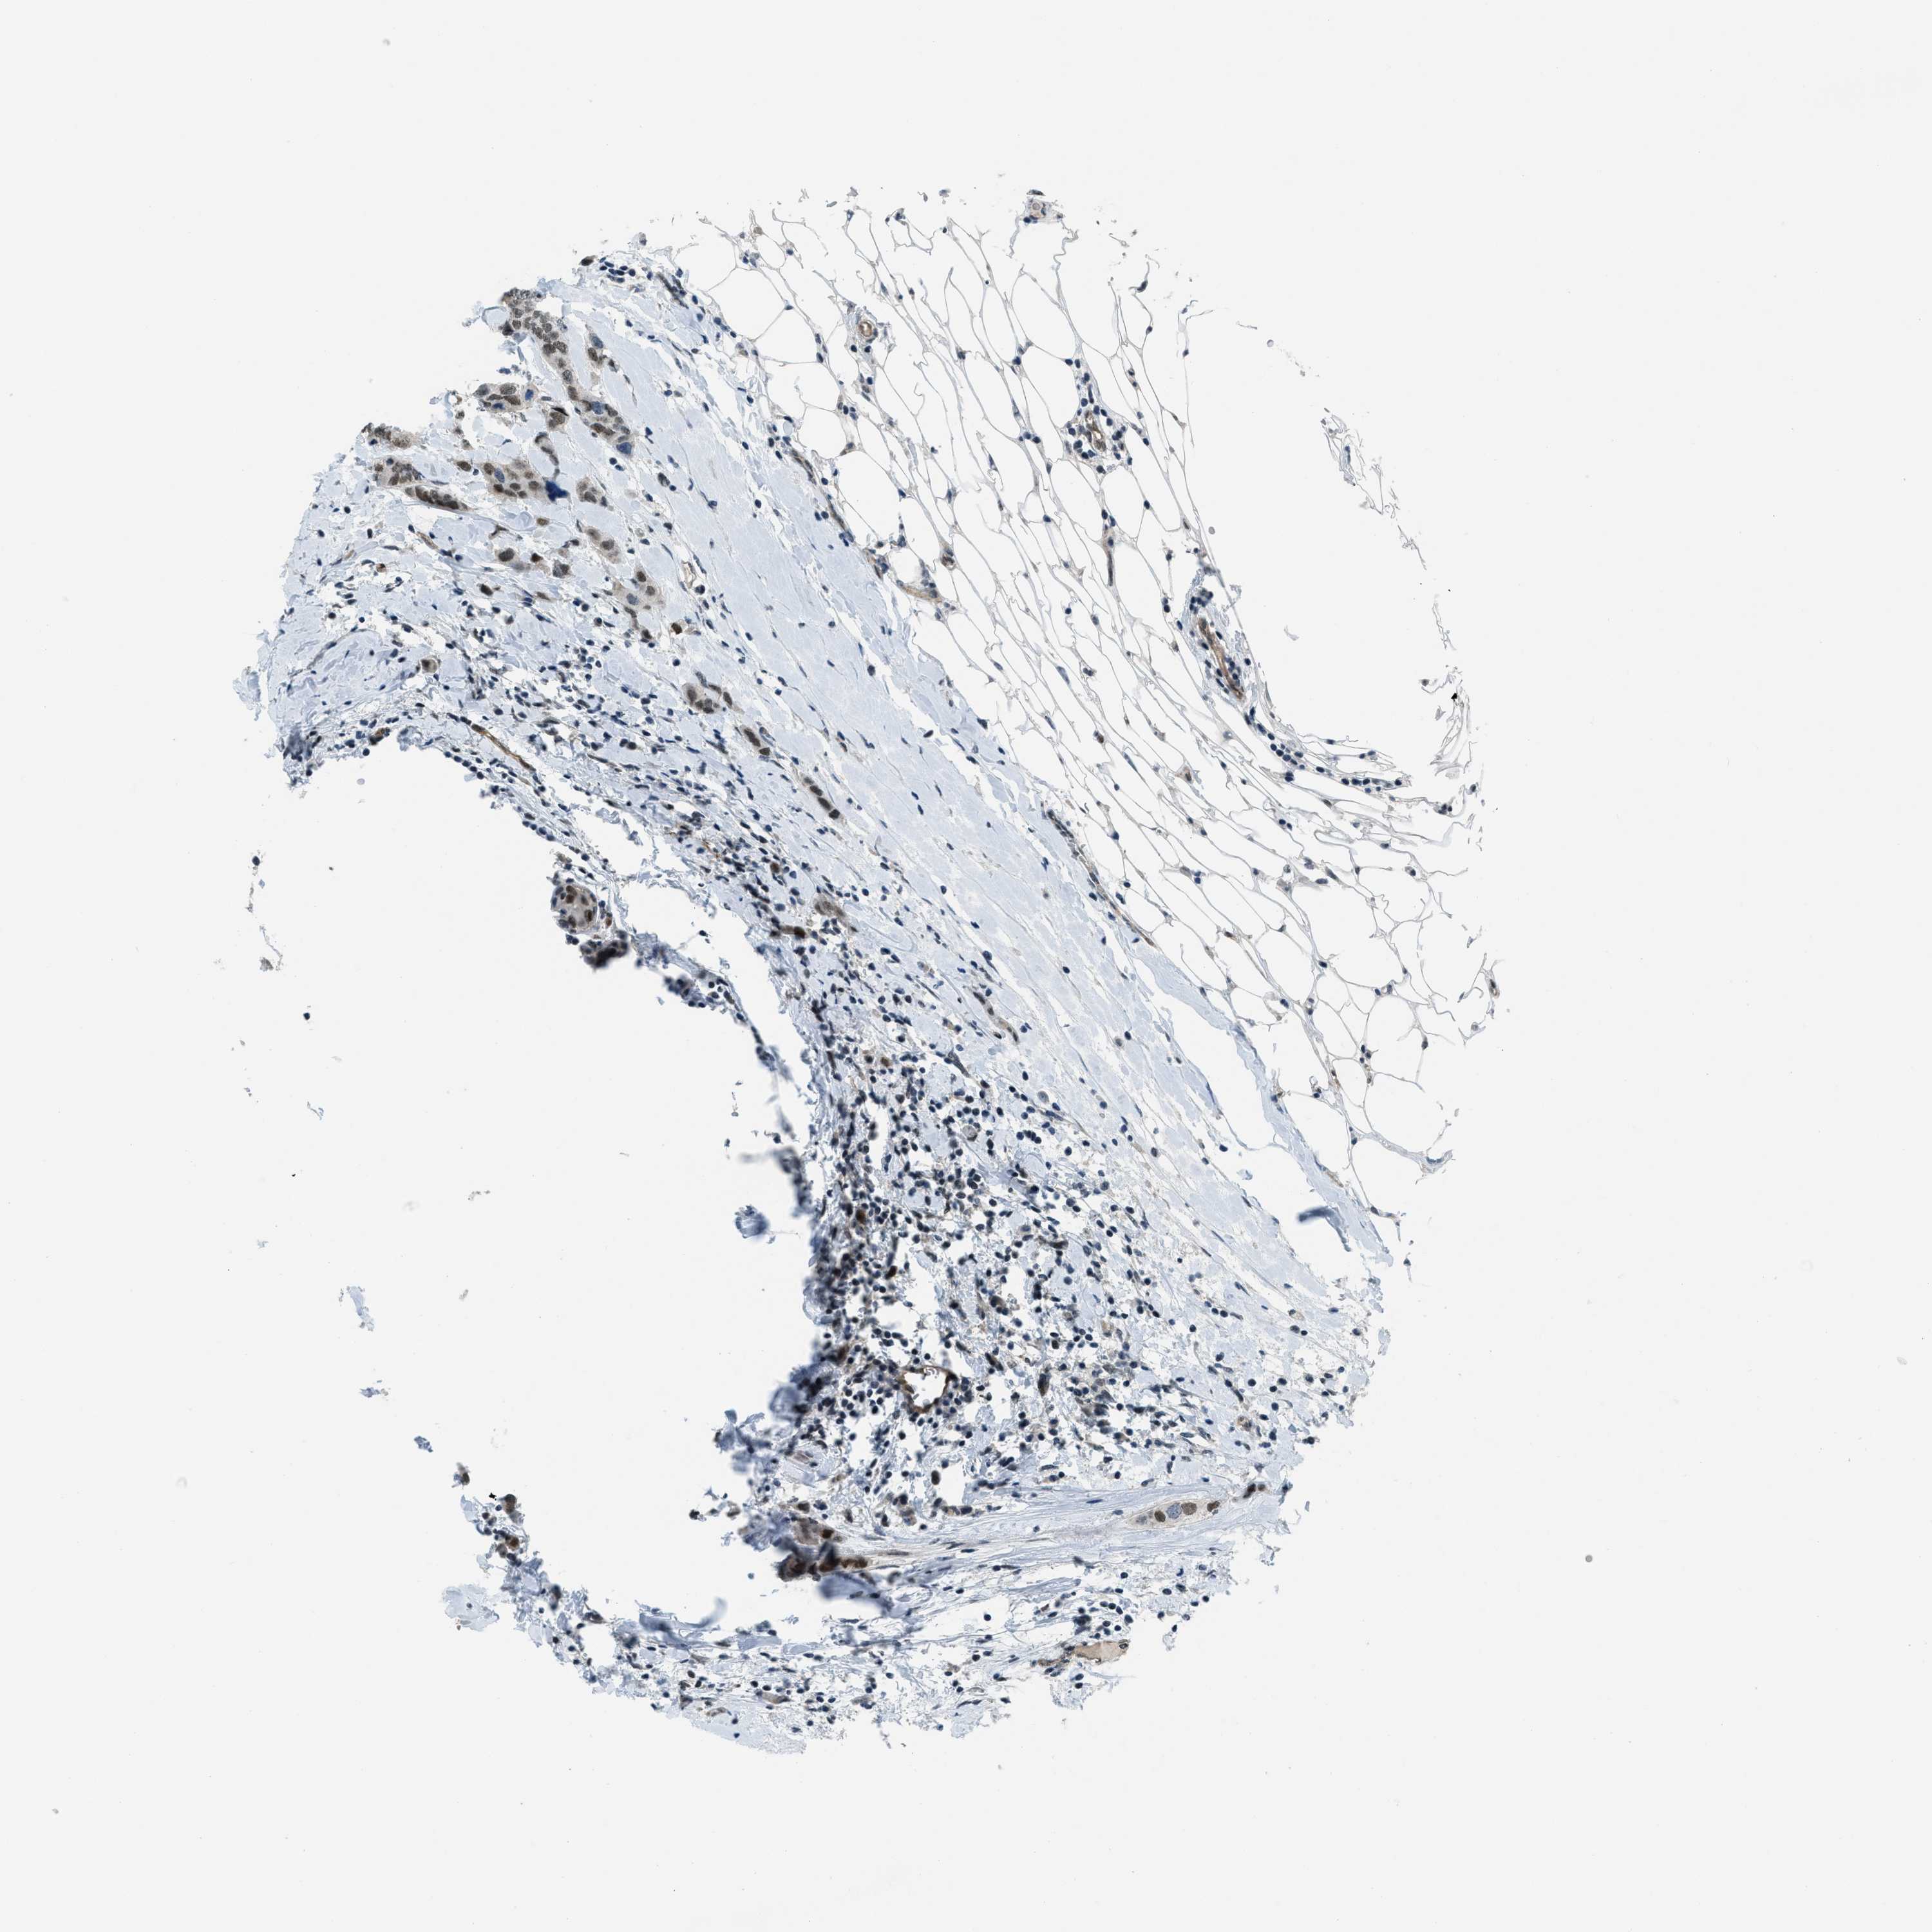

CANCER BREAST CANCER Show tissue menu

BRCA TCGA BRCA VALIDATION PROTEIN EXPRESSION